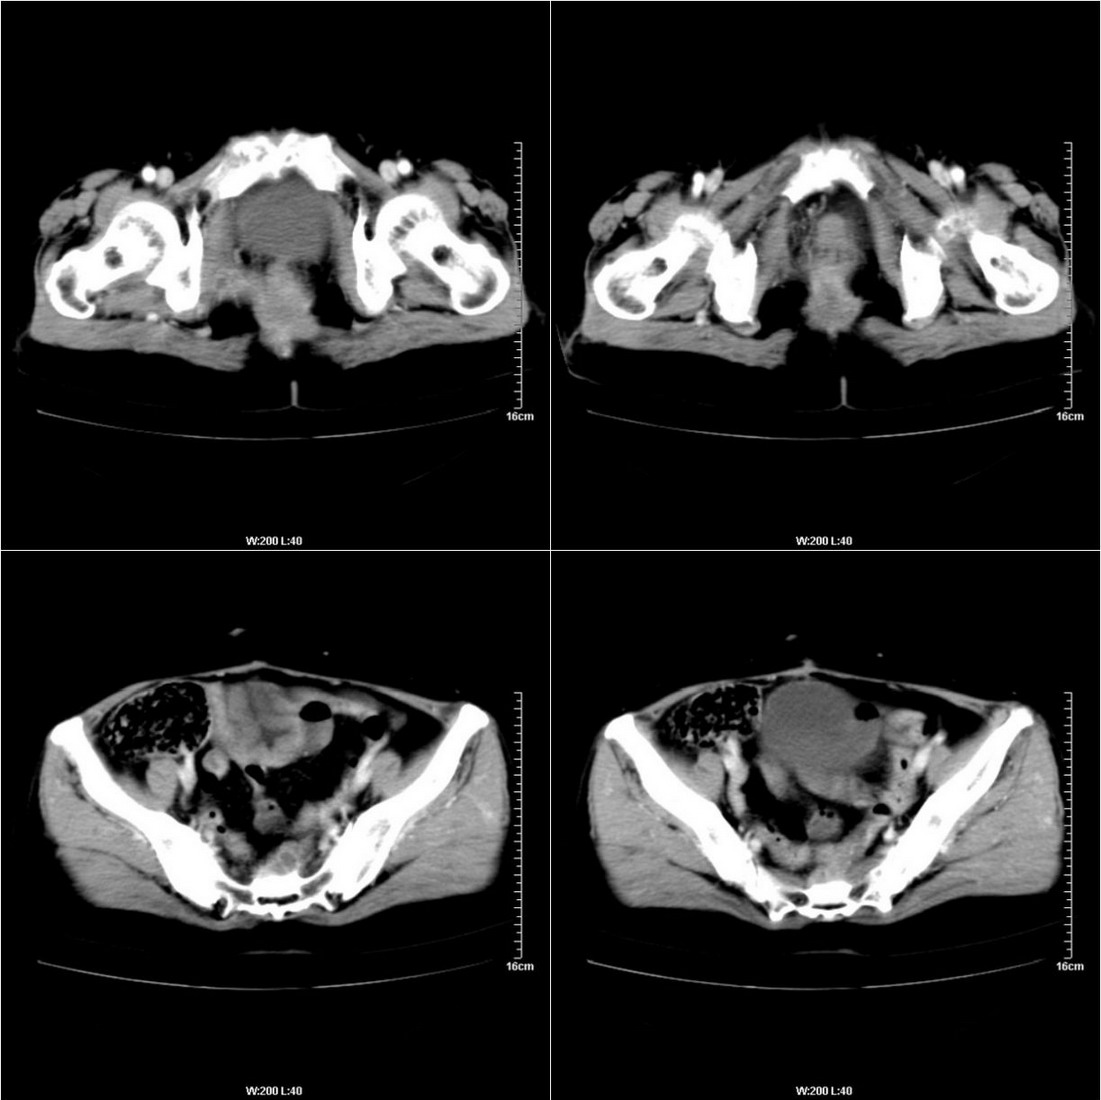

不知道病人的直肠癌手术方式如何,直肠已经全部切除,乙状结肠造瘘于左下腹,肛门应该也没有保留吧?如此,应该是复发了:

病变于肛尾韧带、右侧坐骨肛门窝内并顺右侧肛提肌向右侧闭孔内肌蔓延,骶前软组织内也形成了肿块,麻烦啊!

典型直肠癌术后骶骨前转移复发.

膀胱壁见索条状软组织密度影伴强化,可考虑炎性肉芽肿样增生改变,常见于放疗后或慢性感染;直肠及周围软组织见肿块,轻度强化,考虑直肠癌术后复发,并侵犯周围组织